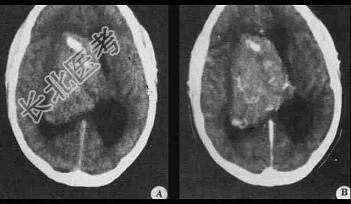

- 单项选择题关于畸胎瘤(如图所示)的描述不正确的是 ( )

A、CT值可低度于脑脊液,也可高至接近骨质

B、良性畸胎瘤境界清楚,有完整包膜

C、通常由2~3个胚层来源的组织构成

D、导致性发育迟缓

E、出现未成熟组织意味恶性程度高